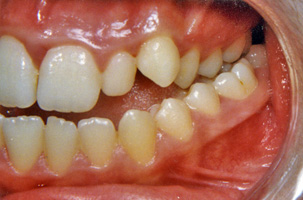

Προβλήματα λόγω της κακής θέσης των γνάθων μεταξύ τους μπορούν με την κατάλληλη ορθοδοντική μετακίνηση των δοντιών να καμουφλαριστούν και να επιτευχτεί μια αποδεκτή σύγκλειση παρά την υπάρχουσα σκελετική ανωμαλία. Παρόλα αυτά, όταν οι διαφορές μεγέθους ή/και οι σχετικές σχέσεις των γνάθων μεταξύ τους είναι έντονες, δεν είναι δυνατή η διόρθωση αποκλειστικά με την ορθοδοντική θεραπεία. Σ’ αυτες τις περιπτώσεις η ορθογναθική χειρουργική είναι απαραίτητη παράλληλα με την ορθοδοντική θεραπεία. Σε μεικτά προβλήματα όπου εμπλέκονται τόσο τα δόντια όσο και ο σκελετός, δεν είναι δυνατόν η ορθογναθική χειρουργική να αντικαταστήσει την ορθοδοντική, αλλά ούτε και η ορθοδοντική μόνη της μπορεί να διευθετήσει σωστά το συνολικό πρόβλημα. Για την αντιμετώπιση μεικτών προβλημάτων υπάρχει συγκεκριμένο πρωτόκολλο συνεργασίας. Ο ορθοδοντικός και ο γναθοχειρουργός μετά από κοινό έλεγχο του ασθενούς παίρνουν τις διαγνωστικές καταγραφές (εκμαγεία, ακτινογραφίες, φωτογραφίες) και αφού μελετήσουν το πρόβλημα, καταστρώνουν το σχέδιο θεραπείας και ορίζουν τις αρμοδιότητες των δυο ειδικοτήτων. Η θεραπεία κατά κανόνα έχει τρεις φάσεις:

1. Προχειρουργική ορθοδοντική:

Ο ορθοδοντικός καλείται να φέρει τα δόντια της κάθε γνάθου σε θέσεις τέτοιες ώστε μετά το χειρουργείο που θα ακολουθήσει, να επιτευχτεί μια ισορροπημένη σύγκλειση. Η διάρκεια της προχειρουργικής ορθοδοντικής θεραπείας είναι δυνατόν να ποικίλλει κατά περίπτωση από 12 έως 24 μήνες.